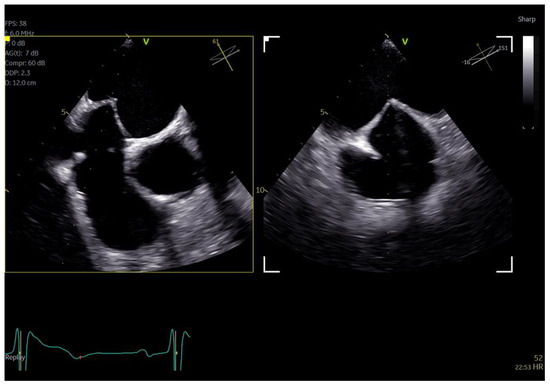

The adult probe was initially inserted for complete 2D/4D image acquisition, followed by the insertion of the pediatric probe while the patient remained under sedation. Remarkably, insertion of the pediatric probe was effortless in all cases, requiring no additional sedation. Despite encountering challenging diagnostic scenarios in all three cases (1st patient: combined severe aortic stenosis and severe mitral regurgitation (MR) due to P1 scallop prolapse, 2nd patient: malfunction of metallic mitral valve prosthesis with an occluded disk, 3rd patient: bioprosthetic aortic valve with paravalvular leak and significant MR in previously MV repair with a complete ring), the pediatric probe consistently provided high-quality images comparable to those obtained with the standard adult probe (Figure 1 and Figure 2, video S4). Notably, there was no compromise in 2D and 4D spatial and temporal resolution, with only minor differences observed compared to the adult 6VT-D probe (Table 1). Evaluation using the 5-point scoring system consistently yielded an average score close to 5 for all three cases, indicating excellent image quality (Table 1).

Figure 1.

Direct comparison of 3D volume −rendered “en face” images of a metallic prosthetic mitral valve with occluded disk. Left image corresponds to 6VT−D adult probe and right image corresponds to 9VT−D pediatric probe.